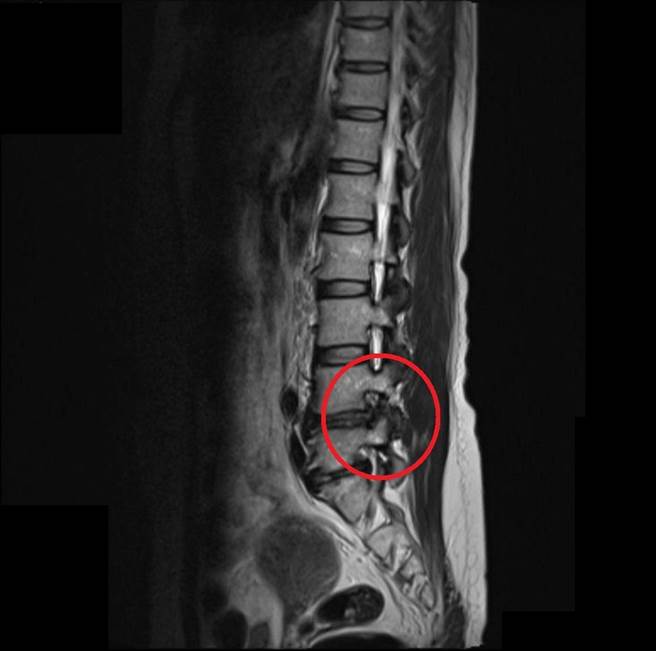

吴女的椎间盘突出压迫神经(红圈处),造成左脚疼痛症状。(大千医院提供/谢明俊苗栗传真)

43岁的吴女在做家事搬重物时,突然听到腰部发出「啪」一声,本来不以为意,但腰部开始越来越痛,行走或身体移位都非常困难,经赴苗栗大千医院门诊就医,院方以核磁共振检查后,证实为椎间盘突出压迫神经。医师以内视镜椎间盘切除手术为其治疗,术后当天疼痛感即消除,隔天就可出院返家,吴女开心的表示:「终于可以恢復正常生活了!」

大千医院骨科医师罗浩儒表示,吴小姐椎间盘突出的位置是在左侧腰椎远外侧,和大部分病人突出在中间的位置不一样。过去传统神经减压手术对于远外侧边的椎间盘突出,必须要先切掉骨头,才能看到突出的部分,然而现行的内视镜椎间盘切除手术可直接以约0.7公分的伤口,直接切除突出部分,大幅降低手术风险。